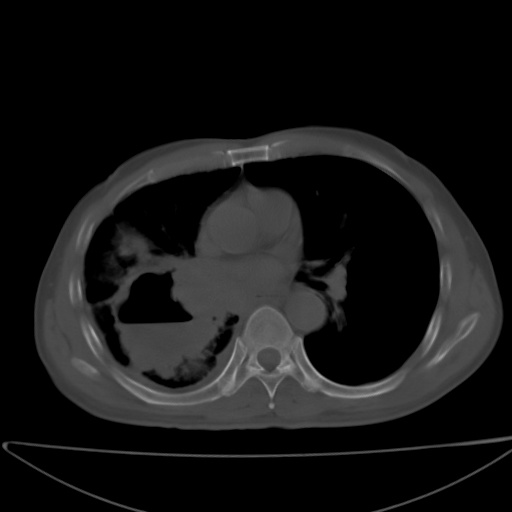

以下是引用jsgdoctor在2008-11-6 22:12:00的发言:[br]右主支气管壁明显增厚,管腔狭窄.考虑为右侧中央型肺癌伴阻塞性炎症\\肺脓肿.

以下是引用zjzjr在2008-11-6 20:25:00的发言:[br]中心型肺ca,合并阻塞性肺炎

以下是引用zsl6918在2008-11-6 19:43:00的发言:[br]右侧中心性肺癌(鳞癌)